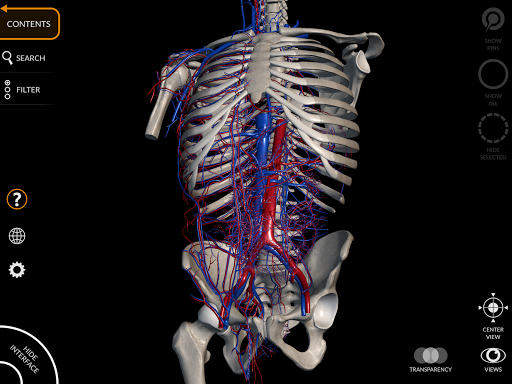

Grâce à une interface simple et intuitive, il est possible d'observer chaque structure anatomique sous n'importe quel angle.

Les modèles anatomiques 3D sont particulièrement détaillés et avec des textures jusqu'à une résolution de 4k.

• Faites pivoter et zoomez chaque modèle dans l'espace 3D

• Option pour masquer ou isoler un ou plusieurs modèles sélectionnés

• Filtrez pour masquer ou afficher chaque système

• Fonction de transparence